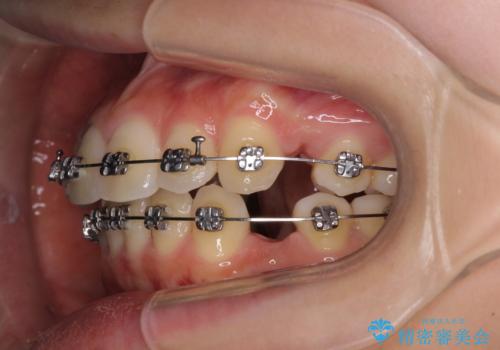

- メタルブラケット

上下左右4本抜歯する場合には、通常2年から2年半ほどの期間を要しますが、僅か1年半で終了することができました。